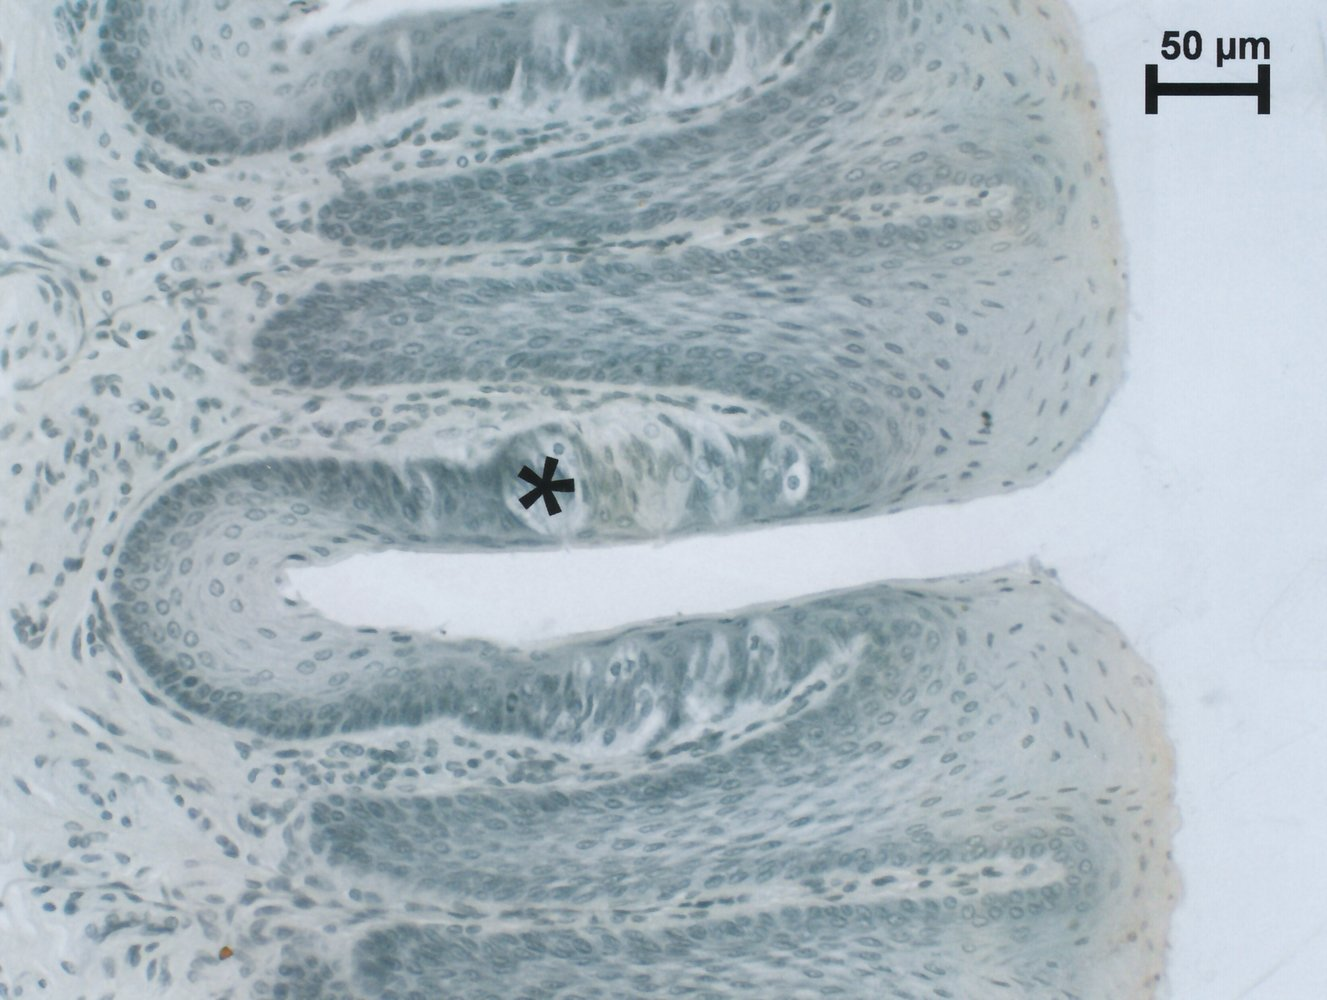

65. Some loop diuretics can cause hearing impairment when used to treat high blood pressure. This side effect occurs due to inhibition of the NKCC1 transporter in cells responsible for the high potassium content of the endolymph in the cochlear duct.

Which letter in the illustration marks these cells?

B